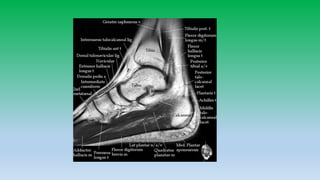

9. T1 coronal image behind the middle facet of subtalar joint ; magnified box shows superficial and deep components of deltoid. The broder deep fibers (Black arrow) run from the medial malleolus to medial process of talus. The superficial fibers (white arrow) run from MM to sustentaculum tali. Open arrowheads shows the flexor retinaculum.